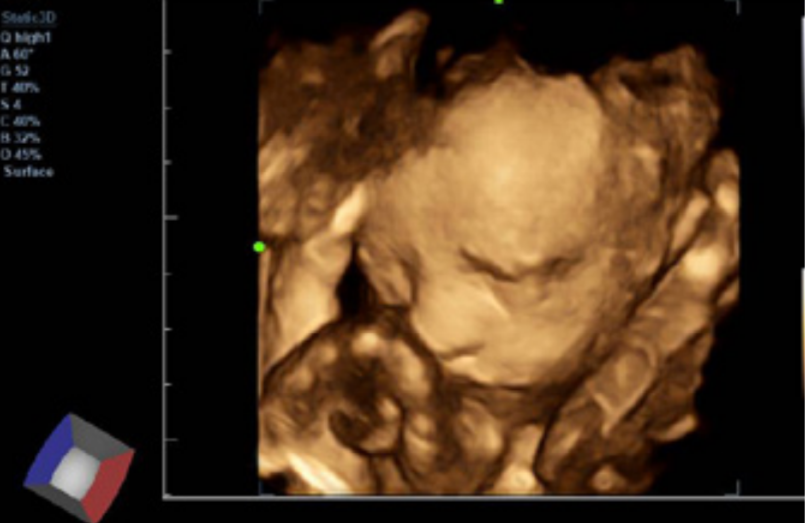

- Posee variadas herramientas que le permite al médico especialista realizar estudios de mejor calidad, como; iClear reducción de moteado, PSH imágenes por armónicos, iBeam formación de imágenes espaciales compuestas.